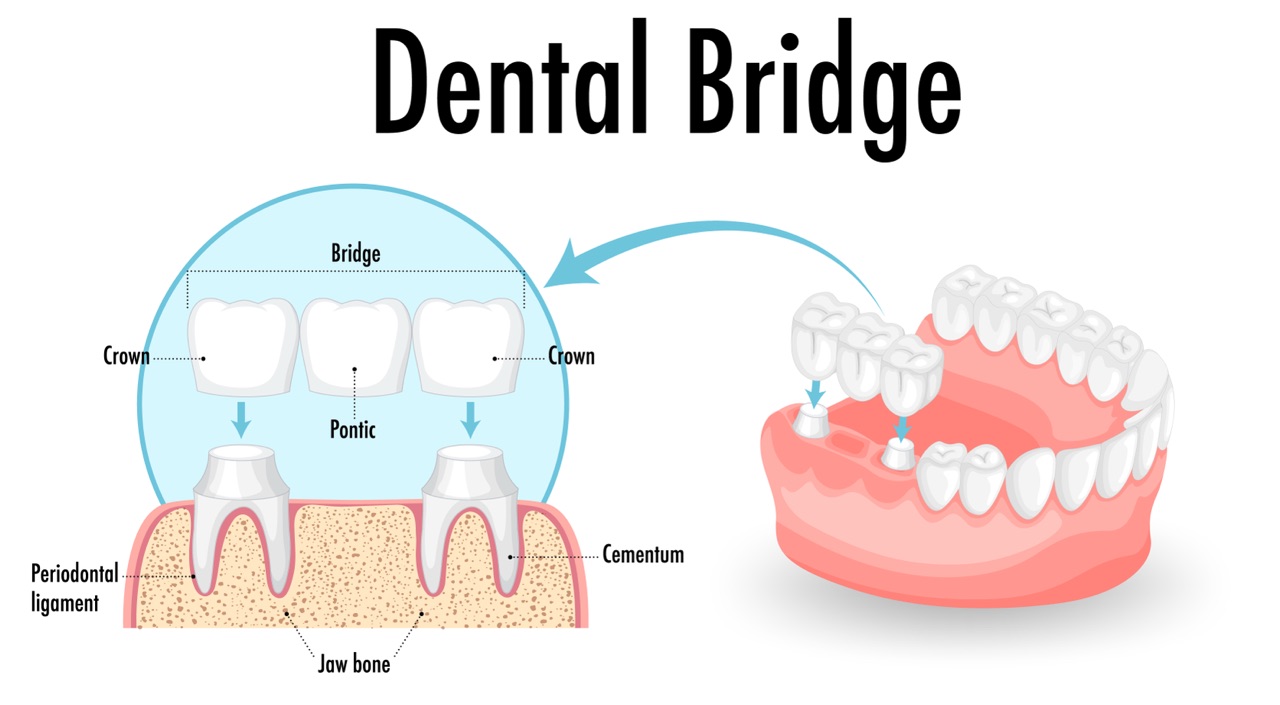

Bridges in Sugar Land

A missing tooth does more than affect your smile — it can impact how you chew, how you speak, and the long-term health of the surrounding…

For patients missing one or more teeth, dental implants represent the gold standard in tooth replacement. A titanium post is placed in the jawbone to serve as an artificial root, which is then topped with a custom implant restoration — a porcelain crown matched to your surrounding teeth. Implants are the only option that preserves jawbone density and provides the feel and function of a natural tooth. For patients missing multiple adjacent teeth, a dental bridge offers a fixed, non-surgical alternative that spans the gap using the neighboring teeth as anchors.